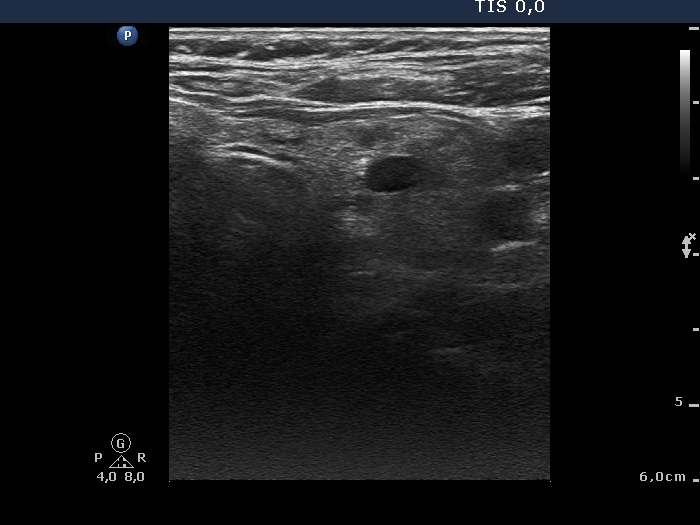

100 consecutive patients with thyroid nodule - Case 26. (ultrasonographic picture 4)

Left lobe, horizontal scan. There is a small cystic lesion in the central part of the left lobe.